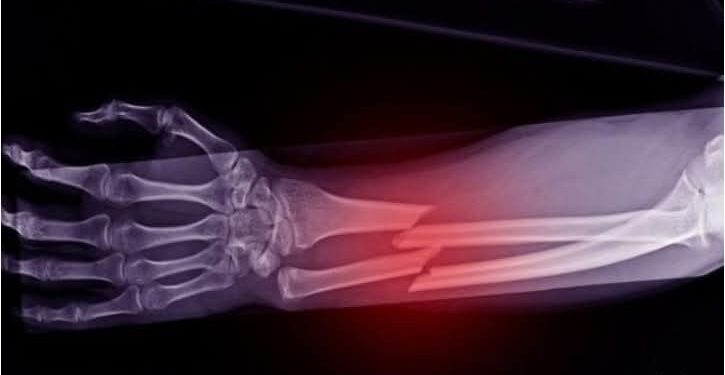

Shkencëtarët kinezë kanë zhvilluar një ngjitës kockash të ri të quajtur ”Bone-02”, që është i aftë të riparojë frakturat në vetëm tri minuta me një injeksion të vetëm, i frymëzuar nga mënyra se si ngjiten ostriket në kushte lagështie.

Ai siguron një lidhje shumë të fortë dhe tretet ndërsa kocka shërohet duke shmangur kështu përdorimin e pllakave metalike ose vidave.